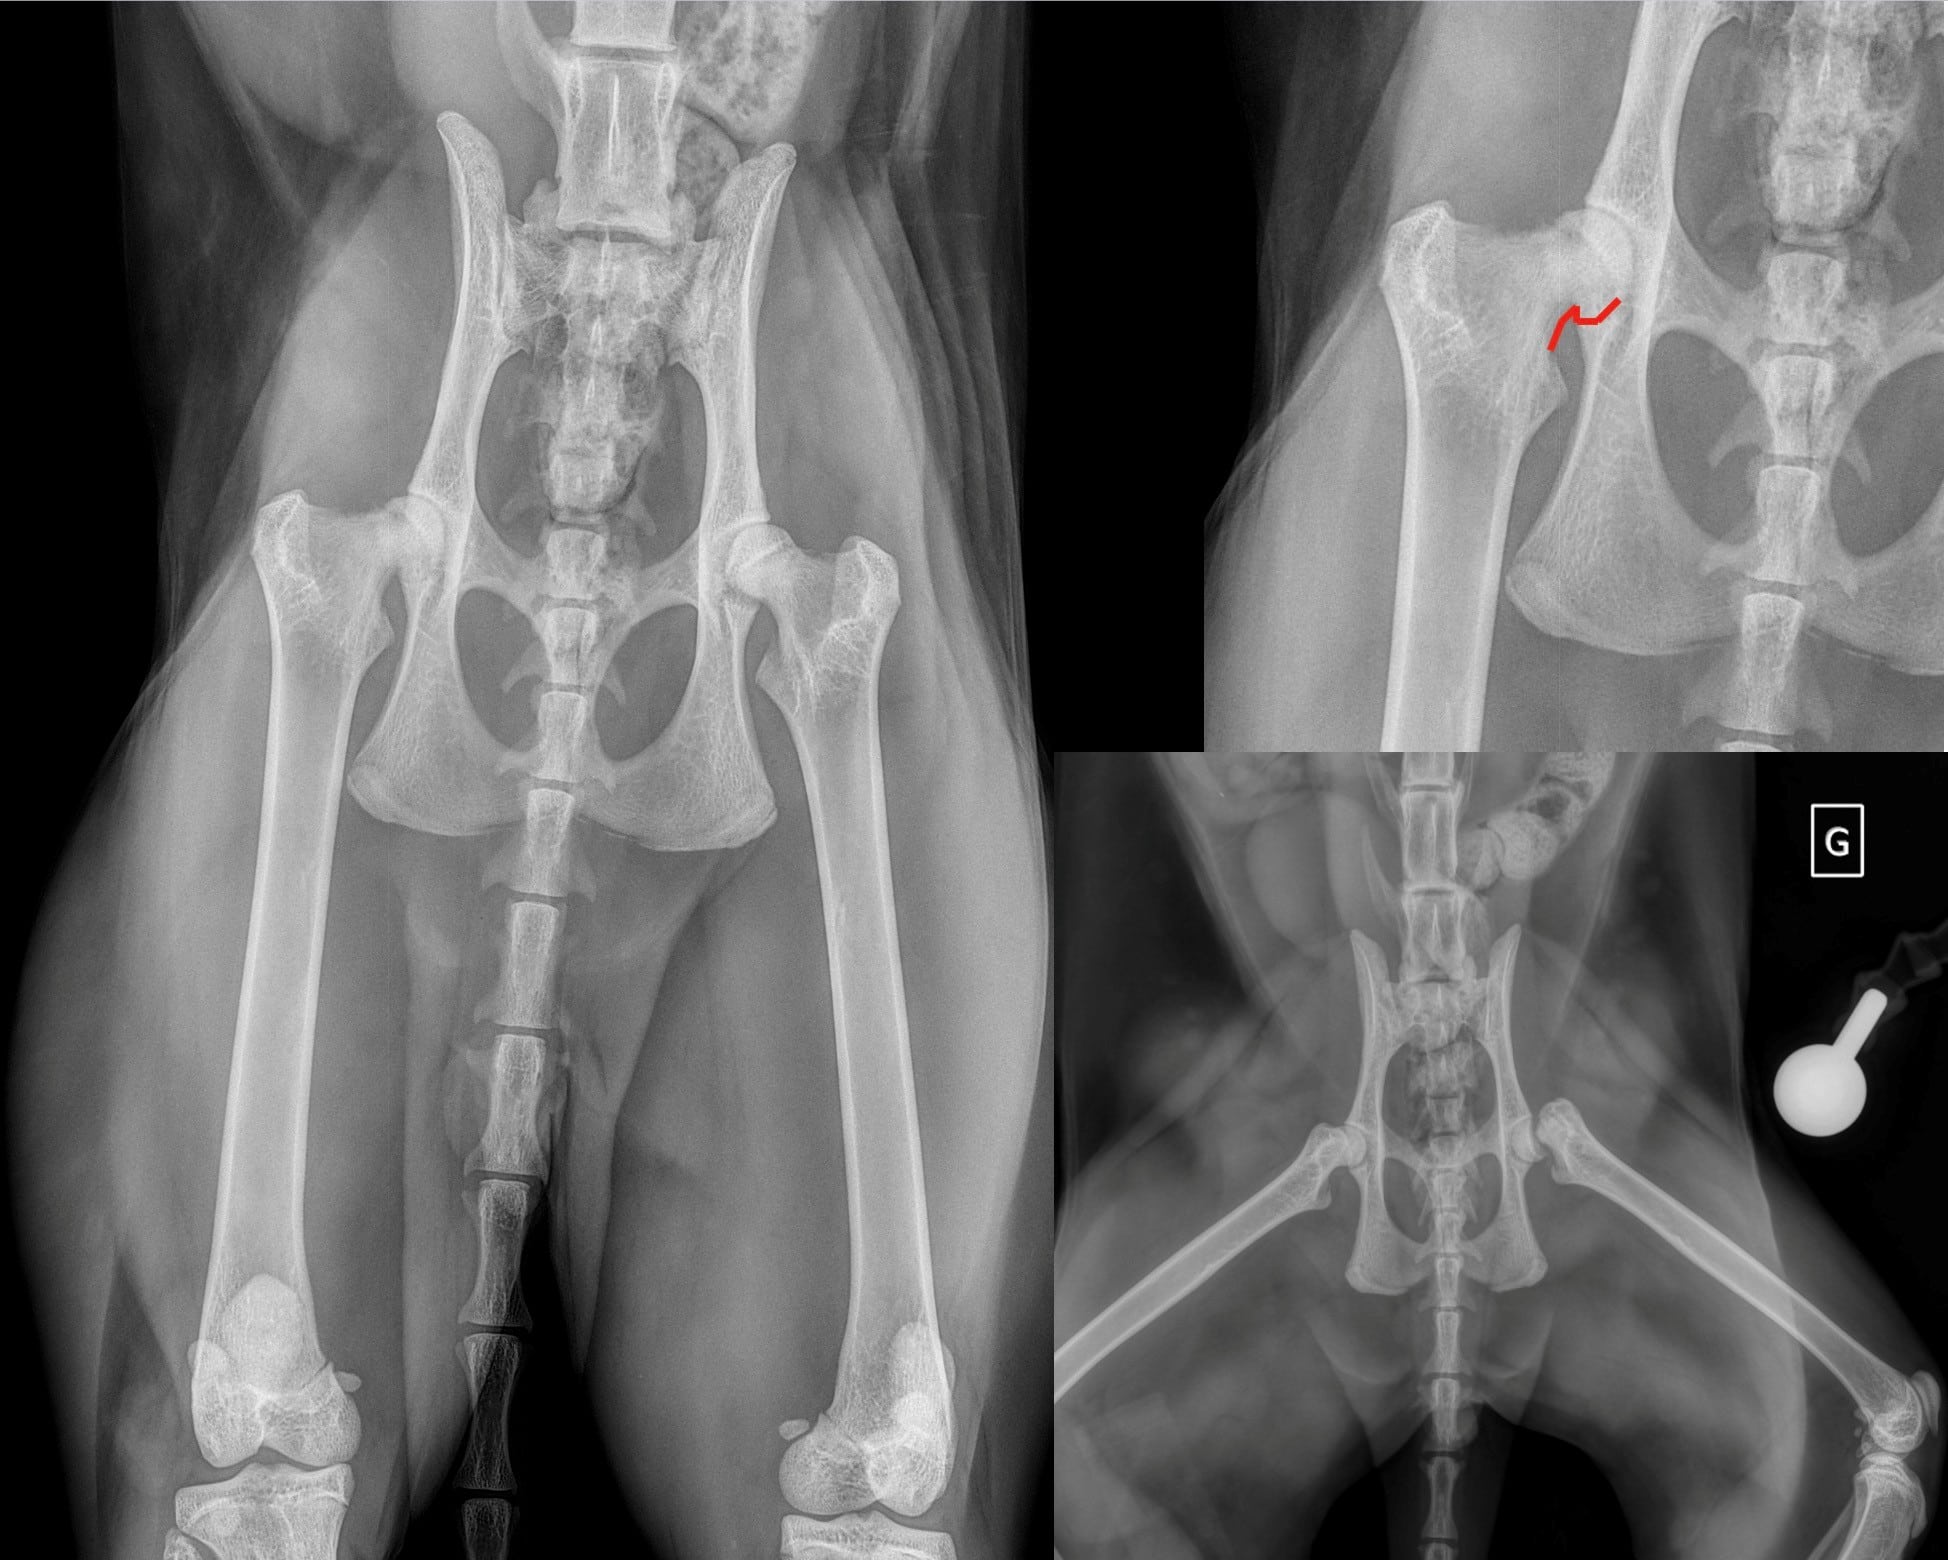

Néanmoins, certaines maladies du jeune ou congénitales sont également rencontrées chez le chat, d’apparition aigue ou progressive, souvent sans traumatisme, parfois associées à des prédispositions raciales : glissement épiphysaire de la tête fémorale, ostéochondrodysplasie du Scottish Fold par exemple. Les chats peuvent également souffrir de dysplasies du coude ou de la hanche, bien que beaucoup moins fréquentes que chez le chien.

A l’hôpital, vous serez reçu par un vétérinaire spécialisé en chirurgie, et même pratiquant exclusivement l’orthopédie. Si possible vous amènerez votre animal à jeun (la boisson est autorisée). Après avoir recueilli les commémoratifs, le vétérinaire examinera votre chat à distance, puis de façon rapprochée. L’examen du chat est plus délicat que celui du chien, ils ont tendance à refuser de se déplacer et à moins se laisser manipuler. Un traitement préalable pourra être prescrit pour les calmer avant la consultation. Le vétérinaire est ensuite susceptible de vous proposer des examens complémentaires (dont certains sous sédation ou anesthésie) tels que des radiographies, ou des ponctions articulaires. Nous disposons d’un service d’imagerie qui peut pratiquer des échographies, un scanner ou une IRM du squelette dans des indications précises mais peu fréquentes. La boiterie peut également nécessiter l’avis d’un neurologue ou d’un oncologue, votre animal sera redirigé vers le service adéquat après une première évaluation par l’orthopédiste, s’il suspecte une cause de cet ordre. Dans la mesure du possible la démarche diagnostique est complétée le jour de la consultation mais il peut arriver de devoir reprendre date. Il en est de même lorsqu’une arthroscopie ou une chirurgie s’avère nécessaire. Dans certains cas, un suivi avec le service de physiothérapie pourra être préconisé suivant la chirurgie ou dans le cadre d’un traitement conservateur.